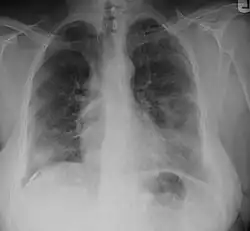

Radiographic image of a person with asbestosis